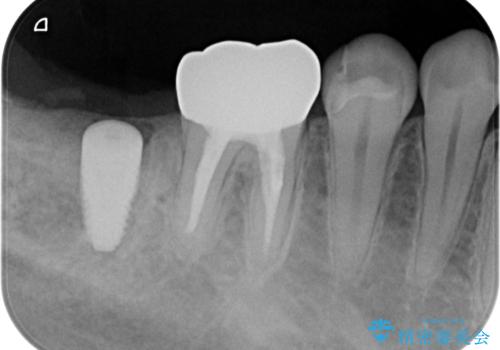

- 右下の奥歯がない状態でしばらく過ごされていた方です。

インプラント入れて噛めるようにしたいとのことだったため、治療を行います。

歯を抜いたまま放置してしまうと、その後の治療が困難になることがあります。

今回はかぶせ物の高さを確保するために、少し顎骨を削り、歯肉の厚みも薄くしました。